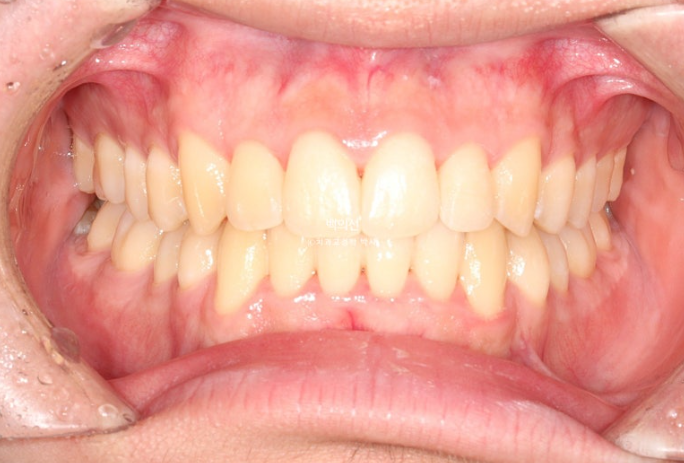

25.08

교합은 물샐틈이 없습니다.

이제 전후 비교 보겠습니다.

토탈 치료기간은 3월부터 7월까지 5개월입니다.